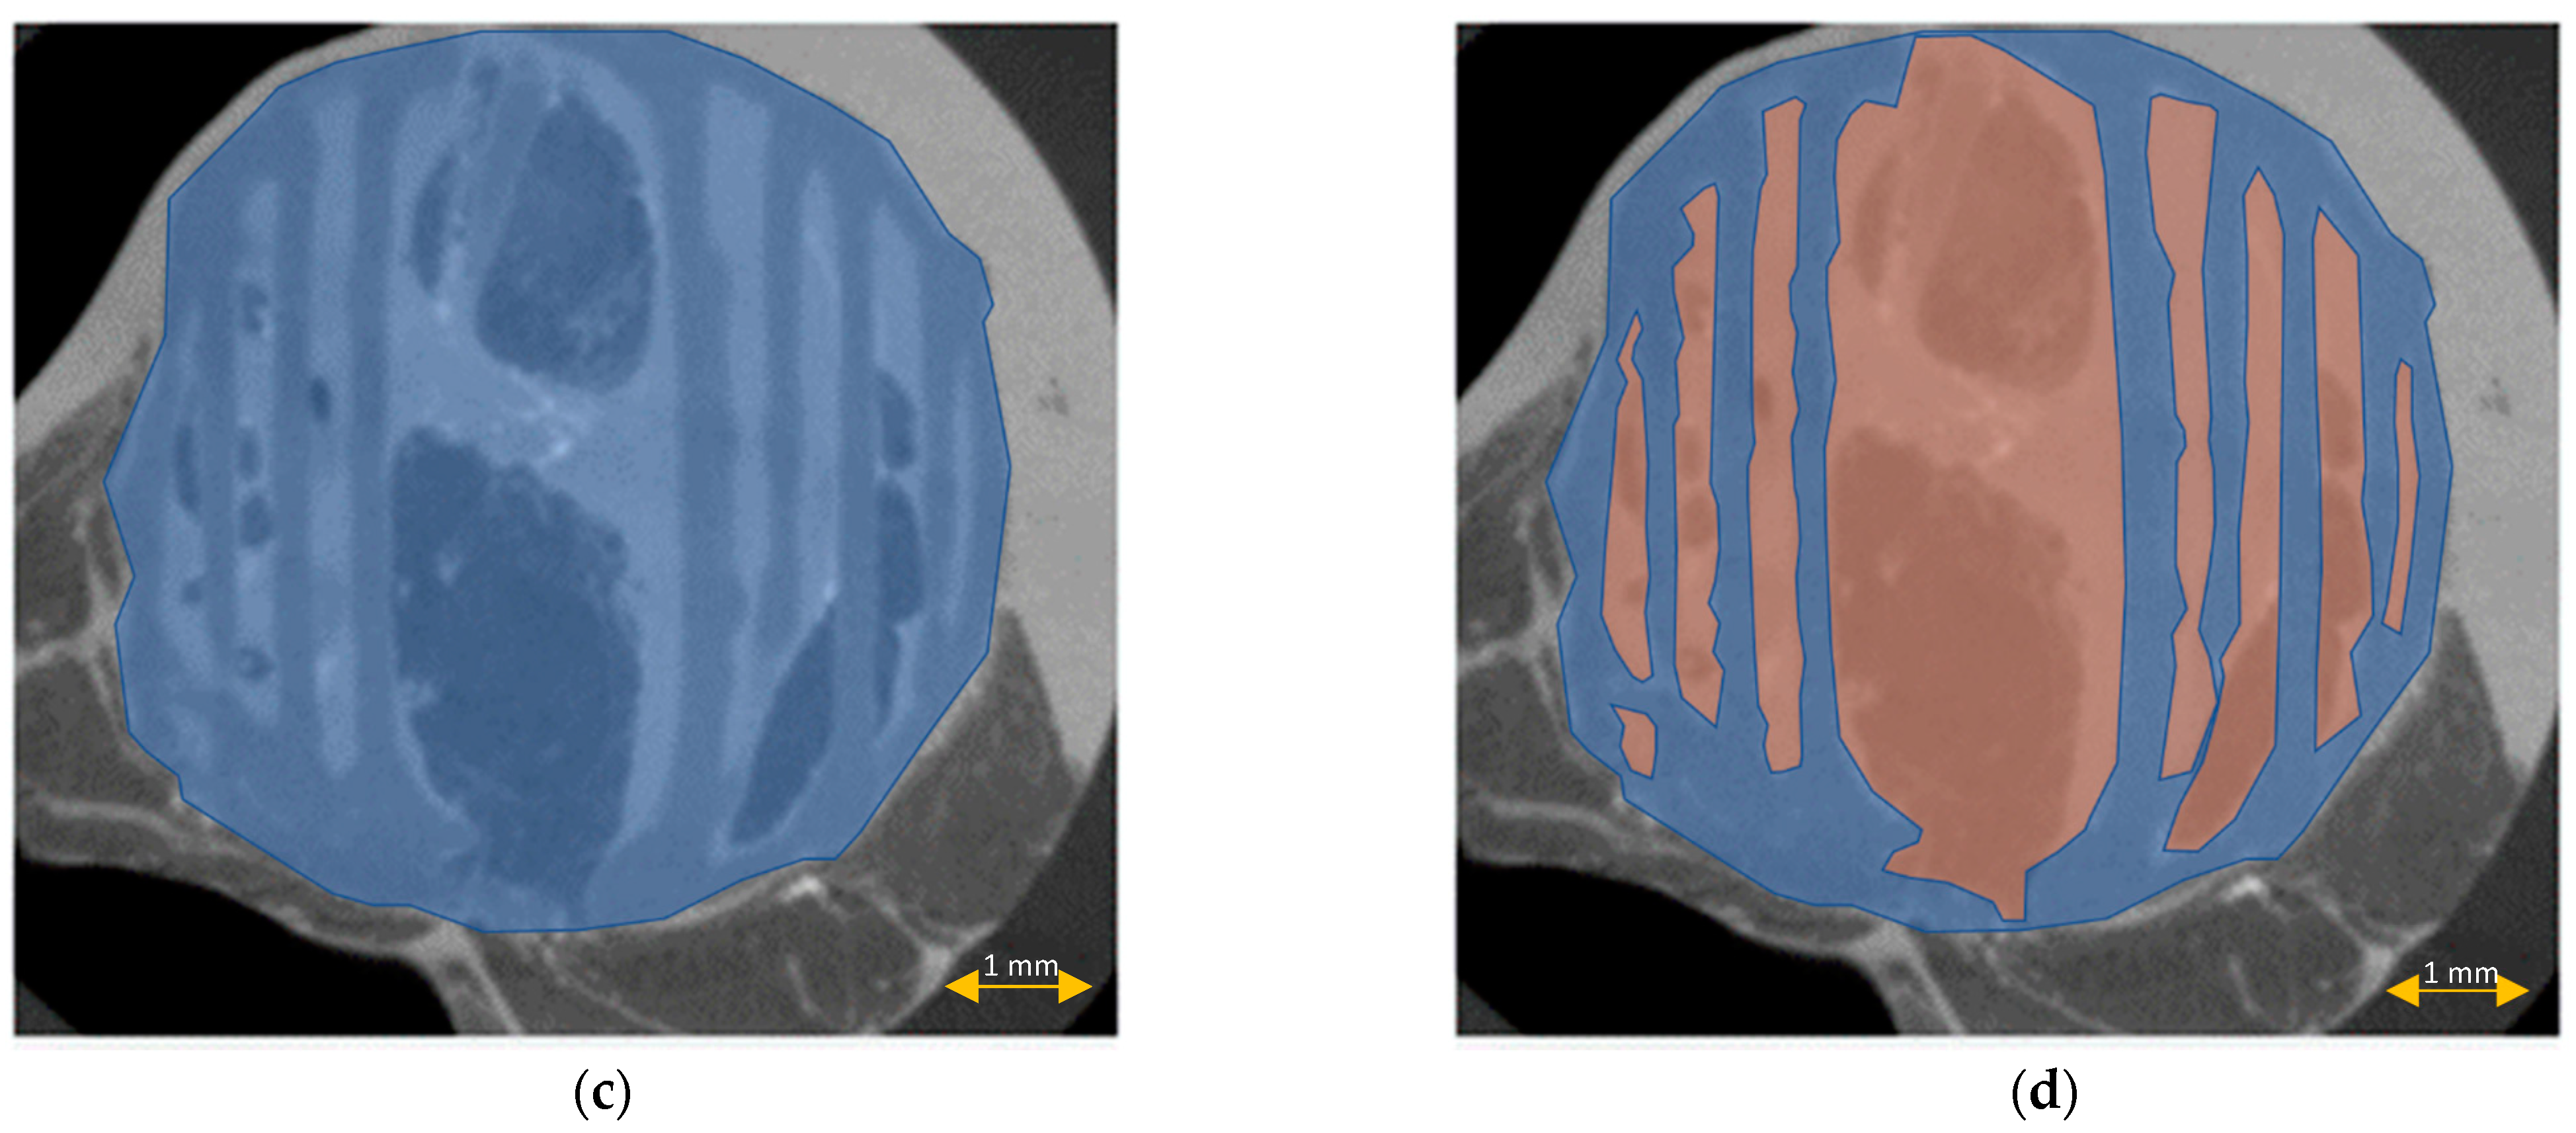

3.5. Scaffold μCT Imaging

3.6. Scaffold Cross-Sectional Analysis